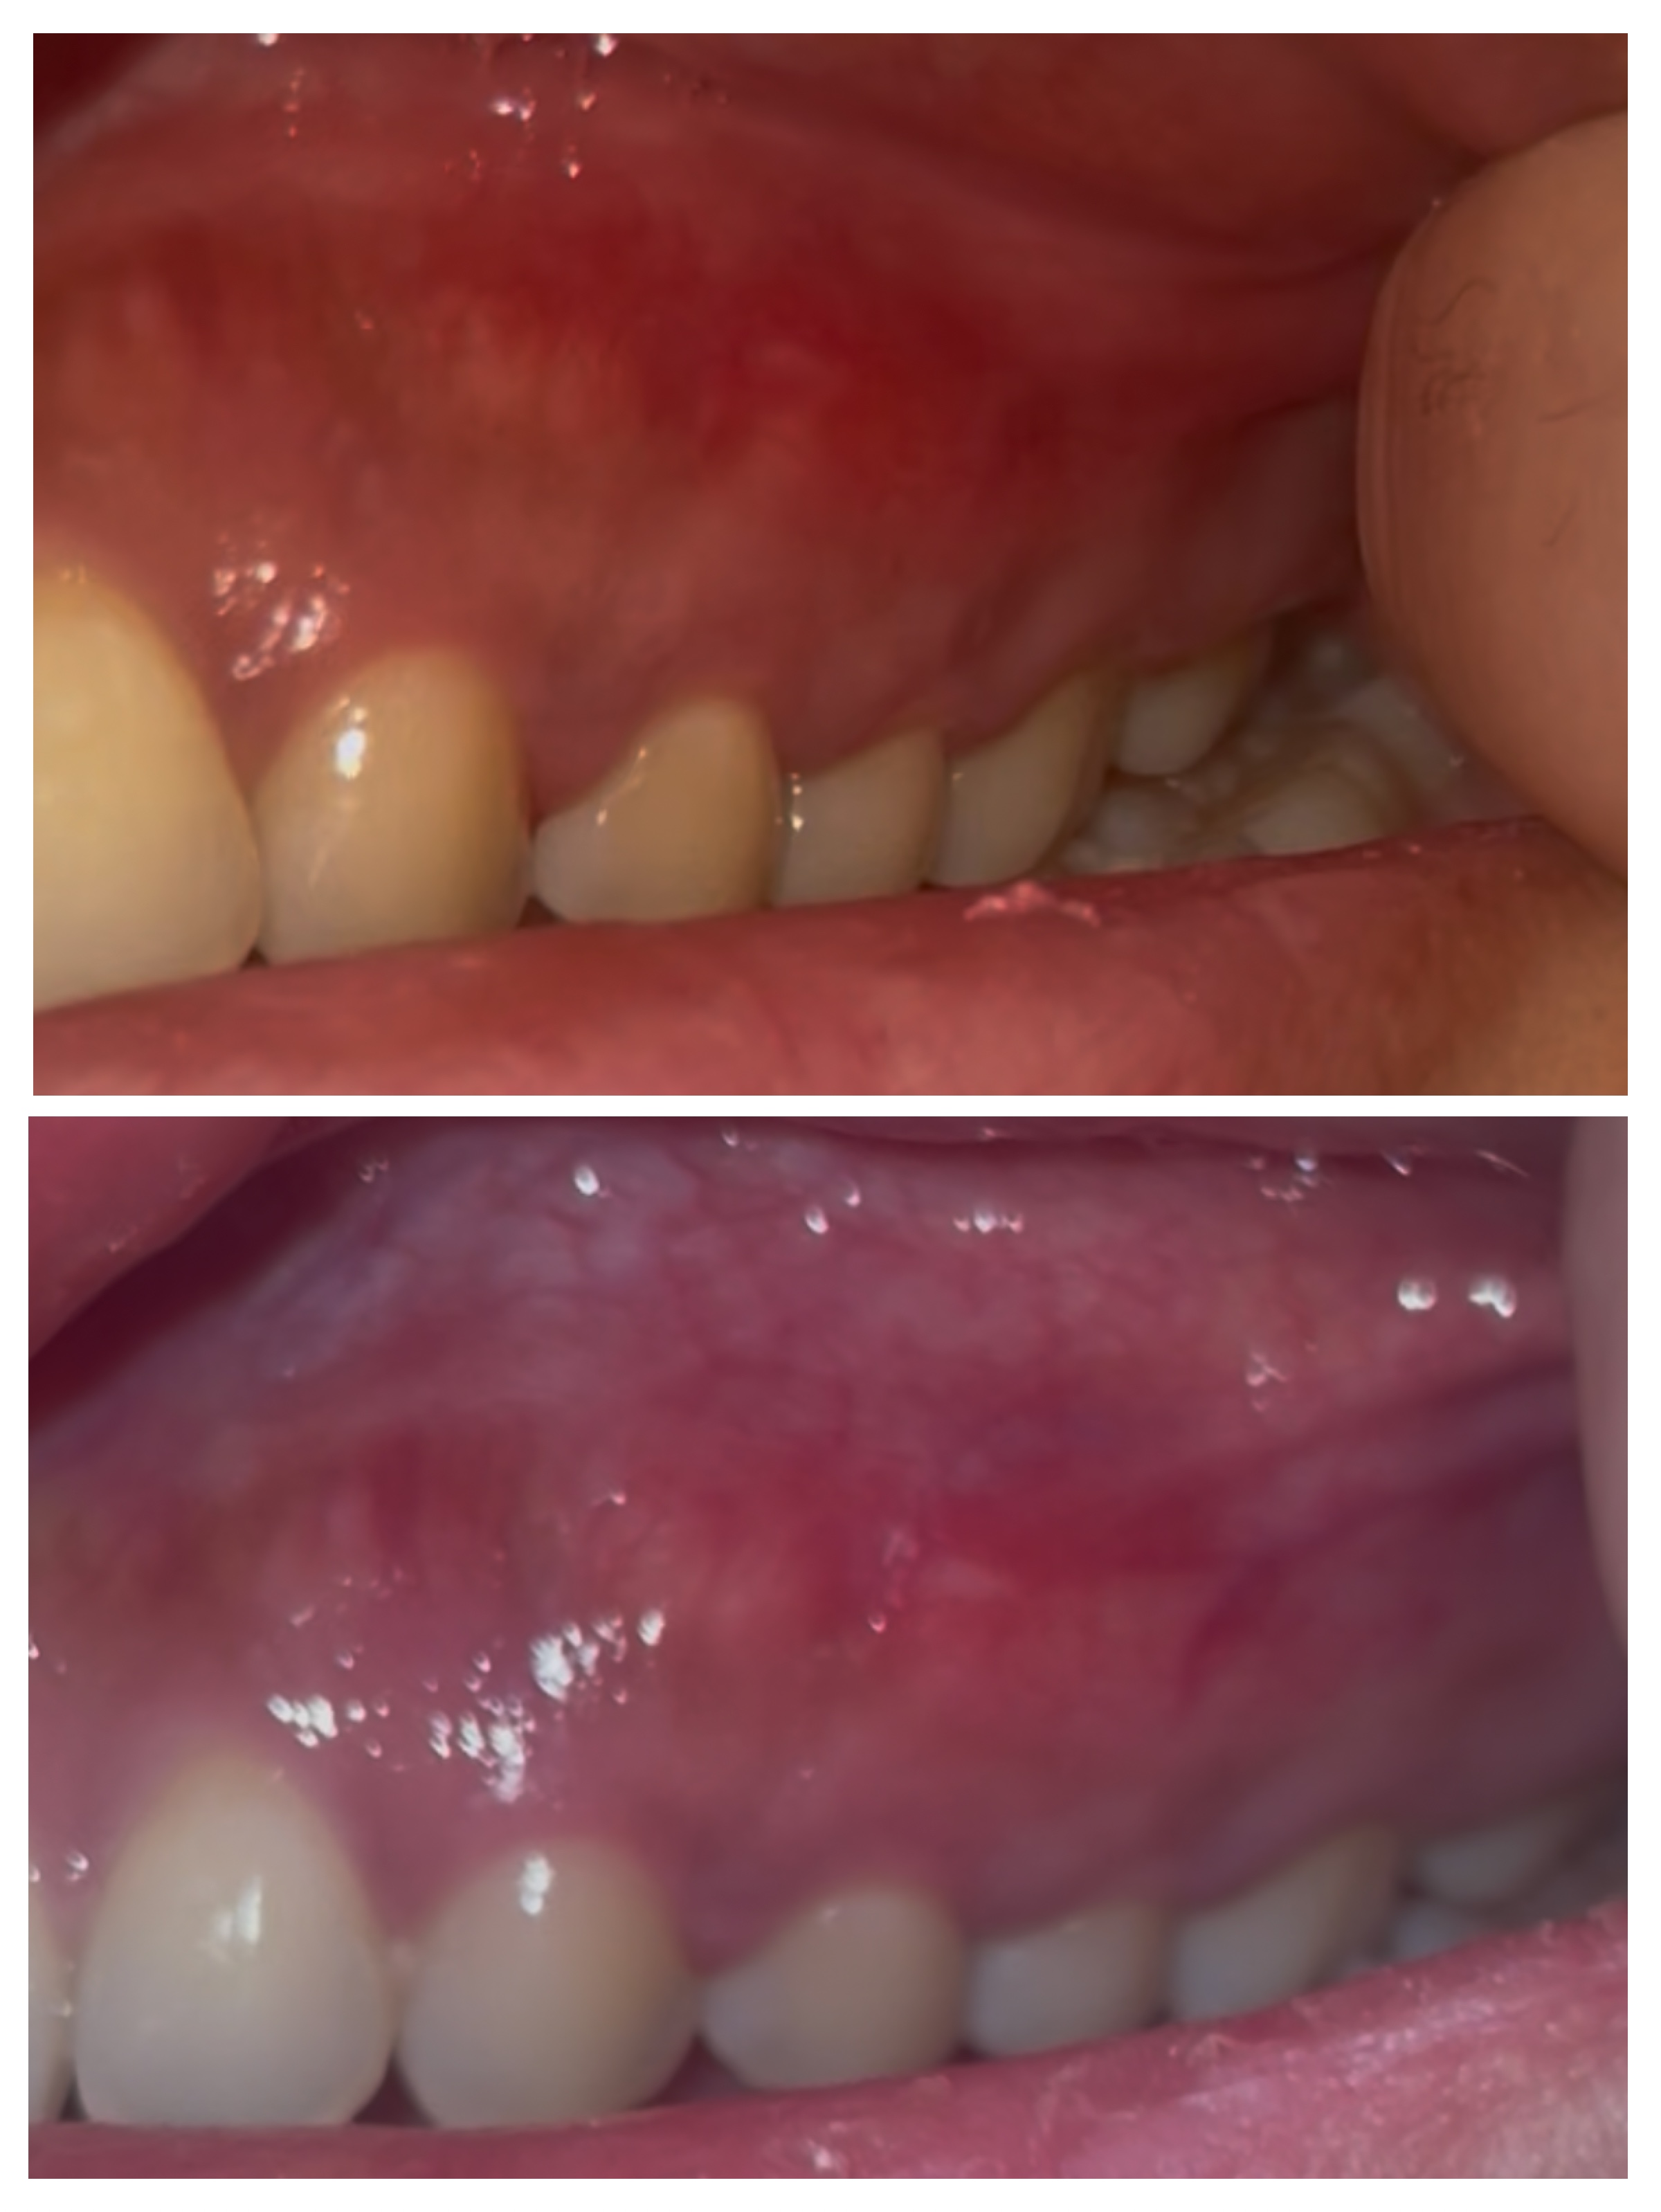

気付いたのは昨日ですが、前歯の歯茎に赤みがあります

痛みはありません

コウハンショウ、もしくは癌の可能性はありますか?

うえの写真が昨日で下の写真が本日です